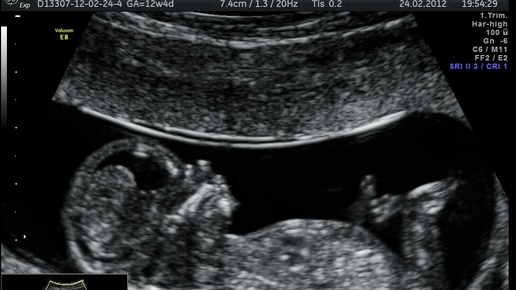

Многие слышали, что УЗИ нагревает ткани и вредит эмбриону. Так ли это на самом деле, сколько раз можно делать УЗИ за время беременности и безопасны ли портативные допплеры для определения сердцебиения, отвечает врач. Эксперт: Маргарита Викторовна Мазуркевич, заведующий отделением ультразвуковой диагностики филиала Родильный дом ГКБ №52, врач УЗИ, акушер-гинеколог, к.м.н. Сколько раз обычно делается УЗИ за время беременности? Согласно клиническим рекомендациям, УЗИ должно делаться минимум два раза, а по возможности — пять [1,2]...

Почему гинекологи делают УЗИ на ранних сроках беременности? Это же вредно? - испуганно спрашивают пациентки.

Вред от короткого исследования в защищенном акушерском режиме не доказан, а вот польза - значительна. В первую очередь врач исключает внематочную беременность. Нетрудно догадаться, что внематочная беременность расположилась не в матке. Чаще всего у плодного яйца не хватает “здоровья” добраться до полости, поэтому оно пытается прикрепиться прямо в маточной трубе. Трубный вариант - это 98-99% всех внематочных. Жизнь любит казусы, поэтому врачи встречают и более редкие варианты прикрепления: Совсем...